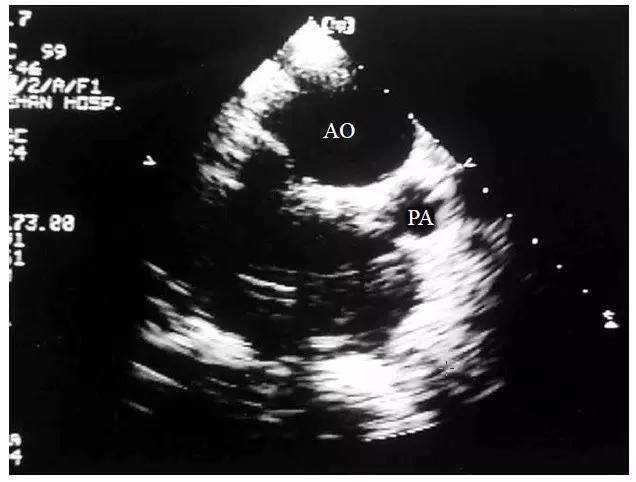

胸骨旁大动脉水平短轴切面能准确反映两根大动脉的空间位置关系,故可作为判断主动脉为左型转位抑或为右型转位的诊断根据。在此切面上,可见两根大动脉的根部同时被横切,呈现一前一后排列的两个圆形大血管横断图像,其外层表现为圆环状,内部为无回声管腔,正常情况时的肺动脉从左侧环绕主动脉半周而向上延续的交叉走行图像消失。若前位的主动脉位于后位的肺动脉的正前方或右前方为右型大动脉转位(图10-4-5);若前位的主动脉位于后位的肺动脉的左前方则为左型大动脉转位(图10-4-6)。

图10-4-5 右型大动脉转位的二维超声心动图表现

胸骨旁大动脉水平短轴切面显示主动脉(AO)位于肺动脉(PA)的右前方